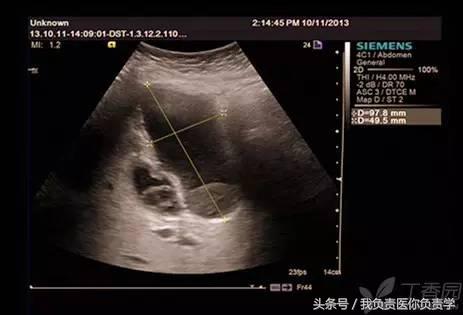

典型病例 4

患者女,79岁,晚餐后出现脐周疼痛数小时急诊。患者无发热,实验室检查示白细胞14×109/L,临床考虑阑尾炎,行超声检查所见如下:

图1示胆囊充盈差,囊壁明显增厚,胆囊周围可见无回声环绕分布

图2为高频探头所见,示胆囊壁肝床侧回声中断,周围可见无回声分布

超声诊断为胆囊穿孔,后经手术证实。